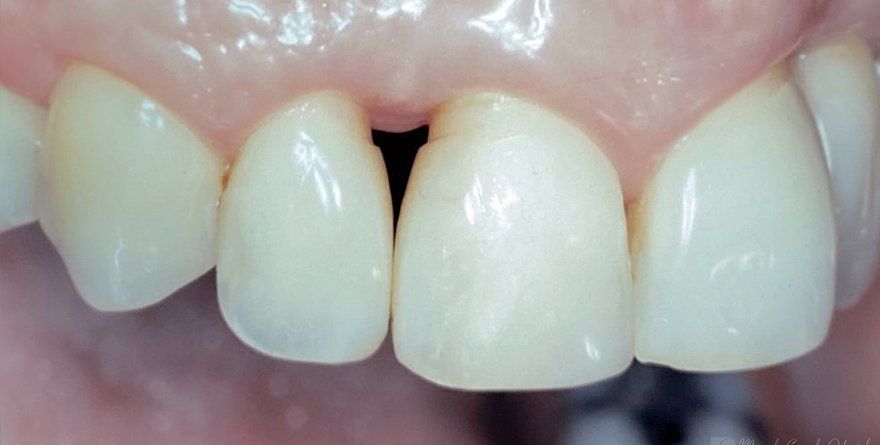

Para casos com boa qualidade de mucosa queratinizada, um envelope vestibular recebe a porção desepitelizada do enxerto pediculado.